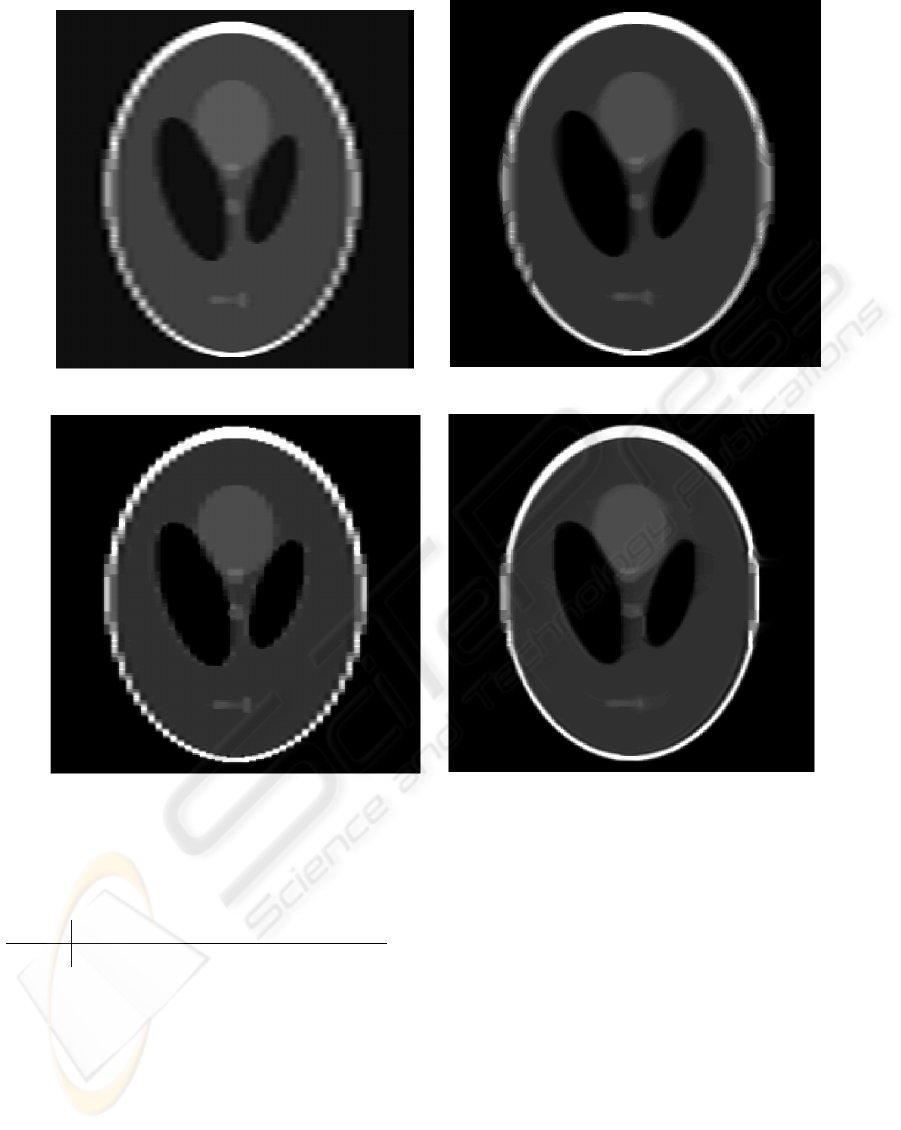

This paper presents a novel method for upsampling anisotropic medical gray-scale images. The resolution

is increased by fitting an image function, modeled by cubic B-splines, to the slices. The method simulates

the observed slices with an image function and iteratively updates the function by comparing the simulated

slices with observed slices. The approach handles partial voluming by modeling the thickness of the slices.

Shepp-Logan phantom show promising results, and the approach performs better than methods such as cubic

interpolation and one-way registration-based interpolation.